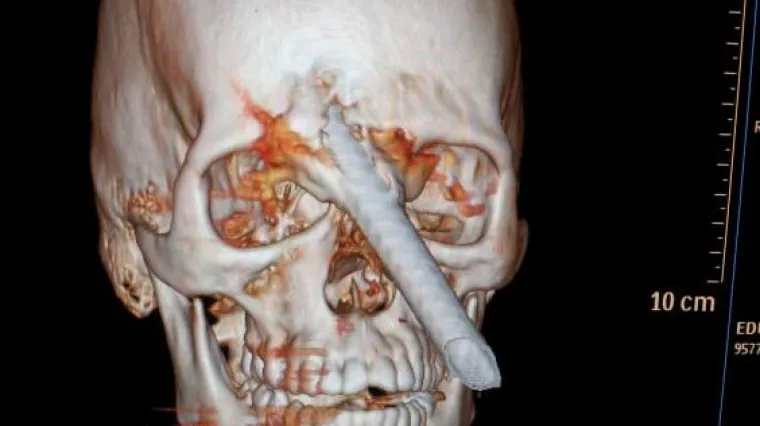

Šipka od dva metra mu probila lubanju, ostao živ

24-godišnjem Eduardu Leiteu šiška je pala s petog kata zgrade u izgradnji te mu prošla kroz mozak, a zaštitna kaciga koju je nosio nije mu pomogla.

Građevinski radnik iz Brazila začudo je ostao živ nakon što su mu liječnici uspjeli iz glave izvaditi šipku od čak 1,8 metara. 24-godišnjem Eduardu Leiteu šipka je pala s petog kata zgrade u izgradnji te mu prošla kroz mozak, a zaštitna kaciga koju je nosio nije mu pomogla. Šipka je probila kost lubanje te izašla između očiju, a operacija vađenja iste trajala je pet sati. Šef kirurškog osoblja bolnice u Rio de Janeiru kazao je kako je pravo čudo što je mladić preživio, a oporavak u bolnici će mu trajati najmanje dva tjedna.